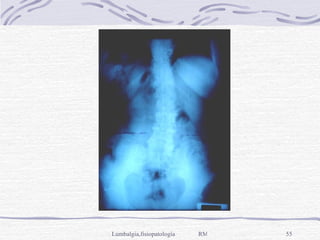

Inflamatoria,  etiología desconocida, en jóvenes, crónica y progresiva, sobre articulaciones sacroiliacas y vertebrales, produce anquilosis, > en sexo masculino, una gran giba al final, con deformación y dolor en pies. Rx: osteoporosis del cuerpo vertebral, sindesmocitos intersomáticos (aspecto de caña de bambú), alteraciones del cartílago,  anquilosis de articulaciones y espóndilodiscitis en 3-6% de casos.

Inflamatoria, etiologíadesconocida, en jóvenes, crónica y progresiva, sobre articulaciones sacroiliacas y vertebrales, produce anquilosis, > en sexo masculino, una gran giba al final, con deformación y dolor en pies. Rx: osteoporosis del cuerpo vertebral, sindesmocitos intersomáticos (aspecto de caña de bambú), alteraciones del cartílago, anquilosis de articulaciones y espóndilodiscitis en 3-6% de casos.